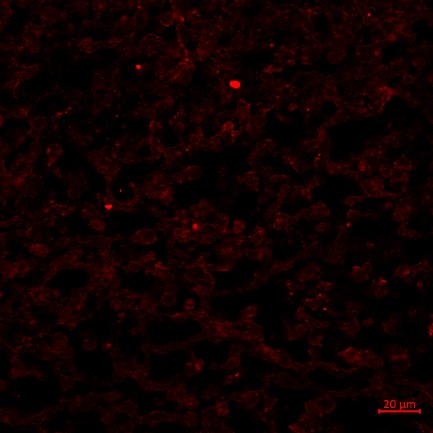

13、免疫荧光实验结果(小鼠肿瘤CBS抗体举例)

免疫荧光实验结果解读:选择激光共聚焦显微镜观察细胞核经DAPI染色后呈现蓝色,目的蛋白被AF594荧光染料标记而呈现红色。